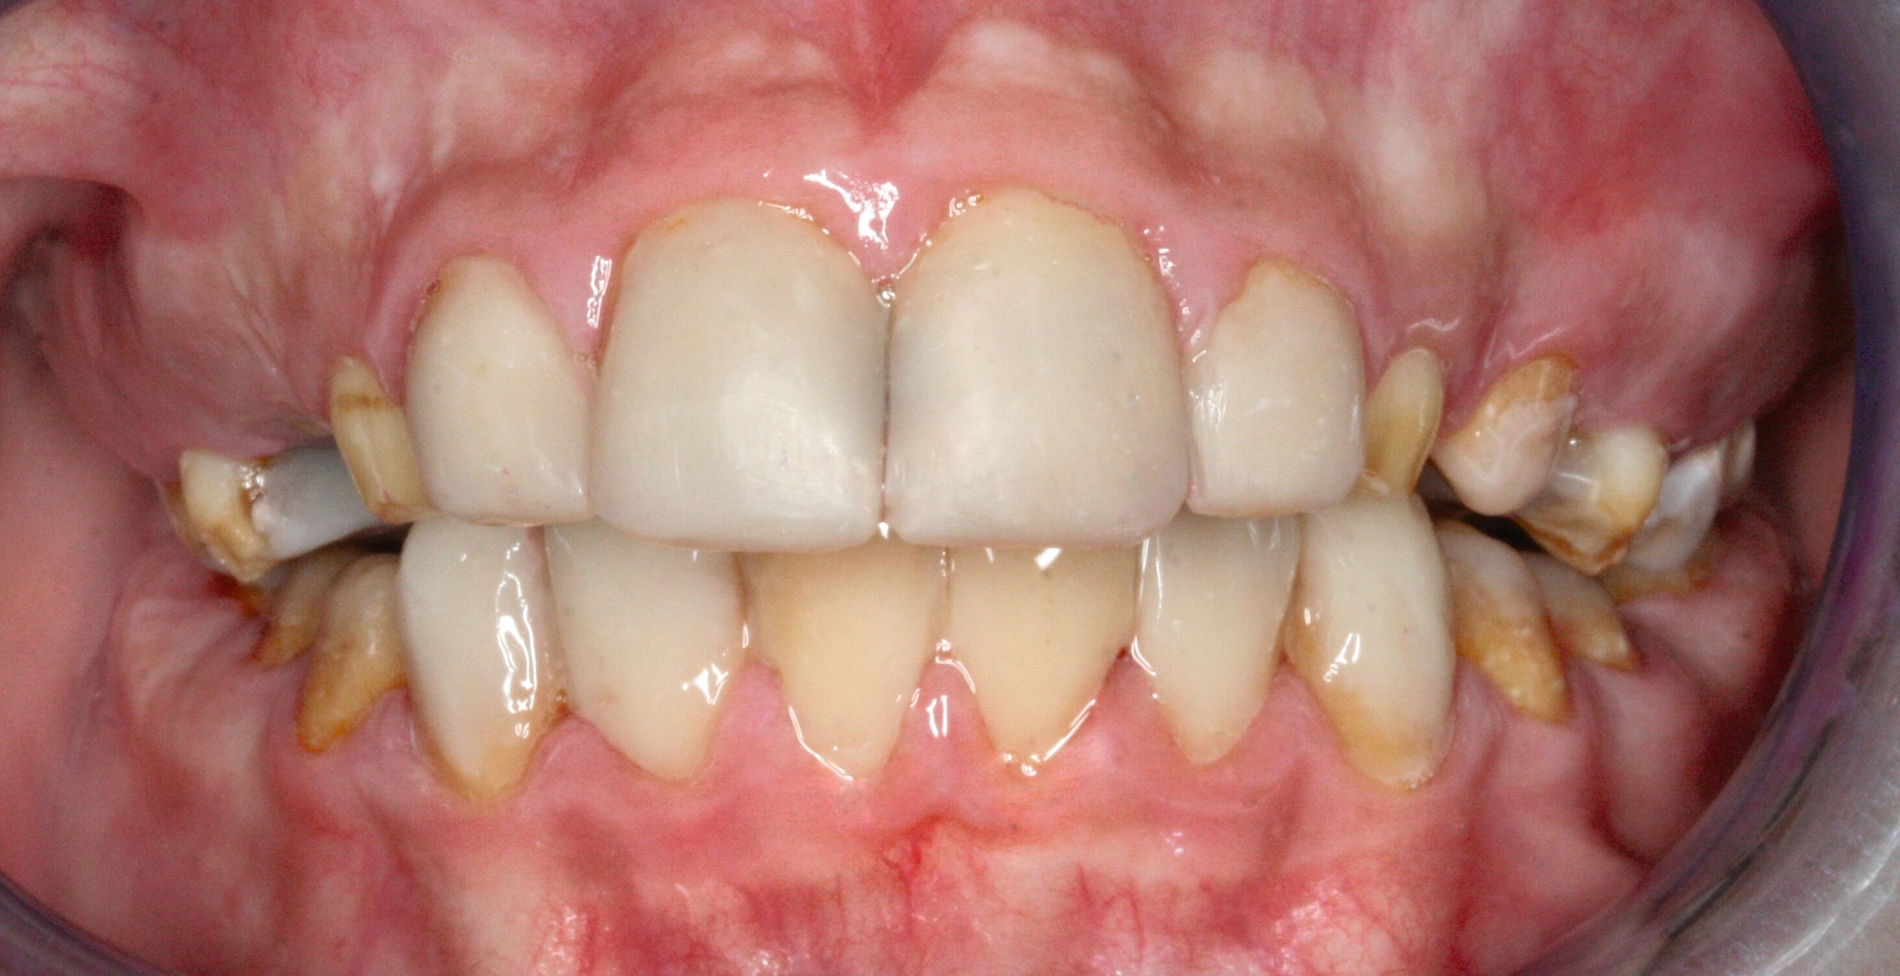

Nach der Extraktion von Zahn 64 wurden die übrigen kariösen Milchzähne nach Konditionierung (Prime&Bond NT, Dentsply Sirona) mit Kompomer (Dyract extra, Dentsply Sirona) versorgt. Für die Frontzahnbehandlung wurde zunächst ein Wax-up auf Situationsmodellen erstellt (Abbildung 3), anschließend eine Silikonformhilfe angefertigt. Nach Reinigung und 3-Schritt-Etch-and-Rinse-Konditionierung (OptiBond FL, Kerr) unter relativer Trockenlegung wurden die Zähne in Mehrschichttechnik mit einem Mikrohybrid-Komposit (Herculite XRV, Kerr) versorgt. Die Seitenzähne wurden wegen des ausgeprägten Würgereizes unter absoluter Trockenlegung mit fließfähigem Komposit (Tetric flow, Ivoclar Vivadent) temporär rekonstruiert (Abbildung 4).

Im Verlauf zeigte sich eine deutliche Verbesserung der Mundhygiene, vermutlich begünstigt durch die regelmäßigen Instruktionen sowie die reduzierte Empfindlichkeit nach Fluoridierung und Restauration. Der Patient war mit dem ästhetischen Ergebnis zufrieden. Seitens der Erziehungsberechtigten und aus zahnärztlicher Sicht bestehen jedoch noch Optimierungsmöglichkeiten hinsichtlich Form, Transluzenz und Politur. Die Nachsorge erfolgt in dreimonatigen Intervallen mit Kontrolle und Wiederholung der Mundhygieneinstruktionen. Durchbrechende bleibende Zähne werden zeitnah mit Komposit versorgt. Langfristig ist eine kombiniert kieferorthopädisch-kieferchirurgische Therapie mit anschließender Versorgung durch indirekte Restaurationen im Erwachsenenalter vorgesehen.